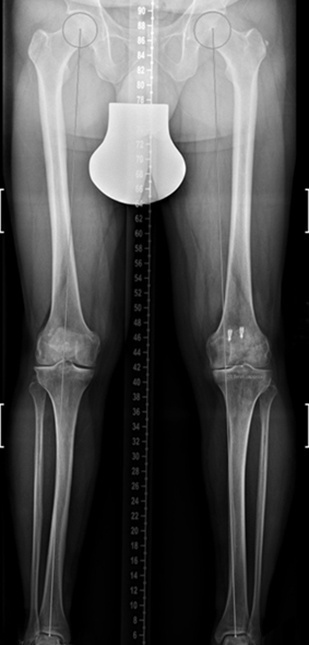

Dr. med. Alexander Strehl: Bei einer Umstellungsosteotomie wird die Lastachse im Knie und somit auch auf den Knorpel korrigiert. Korrekterweise geht die Belastung vom Oberschenkelkopfzentrum zum Sprunggelenkszentrum etwa mittig durchs Knie. Bei O- oder X-Beinen weicht diese Achse ab. Dies kann aus unterschiedlichen Gründen sein, zum Beispiel durch einen früheren Beinbruch oder weil der Patient in der Zeit des Skelettwachstums viel Fussball gespielt hat, kommt aber auch oft ohne eigentliche Ursache vor. Das O-Bein ist häufiger als das X-Bein. Manchmal sieht man diese Abweichung der Beinachse nicht auf den ersten Blick, sondern erst mit einer Ganzbeinstandaufnahme.

Durch O- oder X-Beine wird der Knorpel im Knie einseitig belastet. Da reichen manchmal schon wenige Millimeter, die die Achse abweicht. Folge ist, dass sich eine Knorpelseite deutlich schneller abnutzt als die andere. Mit der Operation wird die Belastung zurück auf die Mitte gesetzt oder eine kleine Überkorrektur auf die gesunde Seite vollzogen, sodass diese etwas mehr belastet und die abgenutztere Seite entlastet wird.

Und was geschieht bei der Operation, damit diese Korrektur erreicht wird?

Dr. med. Alexander Strehl: Bei der häufigsten Umstellungsosteotomie am Unterschenkelkopf macht man einen Sägeschnitt am Knochen, klappt diesen gezielt auf und fixiert ihn mit einer winkelstabilen Platte; dies auf Basis dessen, was man vor der Operation bei der Planung gemessen und errechnet hat. Es entsteht ein winkelförmiger Spalt im Knochen, der von selber wieder zuwächst. Je nach Ort und Art der Deformität findet auch der Eingriff statt. Bei einem O-Bein ist dies meistens am Unterschenkelkopf. Es können aber auch Eingriffe am Oberschenkel nötig sein, vor allem beim X-Bein. Bei extremen Deformitäten kann auch eine Doppelosteotomie erforderlich sein, also dass man am Ober- und Unterschenkel korrigieren muss, um wieder eine gerade Achse zu erhalten. Dies muss man im Vorfeld genau analysieren und planen. Während der Operation wird die Beinachse mehrfach mit dem Ausrichtestab überprüft.